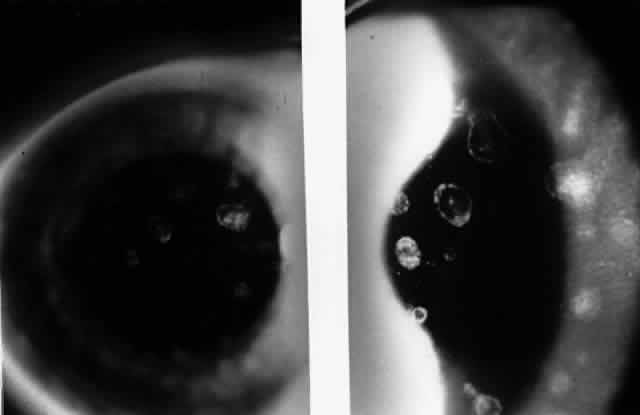

In 1990, Pflugfelder and associates reported a 66-year-old woman with bilateral, pleomorphic, ring-shaped, anterior stromal opacities which developed 3 months after initial onset of concurrent bilateral, dendritic epithelial keratitis (Fig. 5).74 Dendritic epithelium removed by impression cytology at the second recurrence of epithelial disease bound monoclonal antibody to EBV early antigen-diffuse and contained EBV genomic sequences as shown by PCR. Corneal epithelial cultures for HSV were negative on two occasions. EBV serology test did not indicate acute infection, and thus confirmed the earlier impression of Matoba and associates, that EBV keratitis may follow viral reactivation from the chronic carrier state.

Fig. 5. Peripheral corneal dendrite (arrows) in a 66-year-old woman who later developed ring opacities of the anterior corneal stroma.

The pathogenesis of EBV-associated keratitis has not been established; however, the case reported by Pflugfelder and associates74 suggests that epithelial infection by EBV may lead to stromal keratitis. EBV was demonstrated in the dendrite by PCR and EBV-specific monoclonal antibody staining. The epithelial keratitis began 4 days after a chemical facial peel. The chemoexfoliant included phorbol ester, which can induce EBV replication in latently infected B lymphocytes and epithelia and has been implicated as a cofactor in the development of nasopharyngeal carcinoma. Pflugfelder and associates suggested that the keratitis was due to phorbol ester-induced reactivation of EBV latent within corneal epithelium. Although the detection of EBV genome in this case may be due to persistently infected cells in the corneal epithelium, the immunohistochemical evidence of EBV early antigen within the dendritic epithelium indicates a replicative EBV infection was occurring and implicates EBV as the cause of the keratitis. Interestingly, among the patients with EBV stromal keratitis described by Matoba and associates,69 two patients were noted to have punctate epithelial granularity adjacent to stromal opacities. It is unknown whether these epithelial changes occurred as a result of recent EBV replication within the corneal epithelium or were secondary to underlying stromal inflammation.